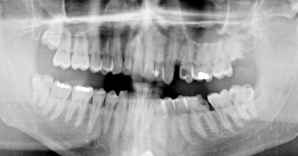

Zur Diagnostik sollte ein sogenanntes Orthophantomogramm - das ist eine Aufnahme von beiden Kiefern - erstellt werden. An Hand dessen kann eine Übersichtsdiagnose und bei Zweifel durch eine oder mehrere Einzelaufnahmen eine genaue Diagnose gestellt werden. Diese Aufnahmen sollten nicht älter als 1-2 Monate sein und mitgenommen werden.

Besonderes Augenmerk ist hierbei auf Weißheitszähne zu legen. Aus diesem Grund sollte ein auch chirurgisch tätiger Zahnarzt aufgesucht werden. Lassen Sie es mich ein bisschen provokant sagen: Weißheitszähne haben auf einer Langfahrtyacht nicht das Geringste verloren. Das wurde unlängst durch den 19-jährigen Johannes Erdmann demonstriert, der unmittelbar vor seiner Atlantiküberquerung eigens wegen einer Weisheitszahnoperation zurück nach Hamburg fliegen musste.

Auf dem Röntgenbild sehen wir vier verlagerte Weißheitszähne, die auf Grund ihrer Lage als Problemfälle anzusehen sind. Speziell der obere linke Weißheitszahn ist schon kariös sehr zerstört. In diesem Fall ist vor einer Langfahrt eine operative Entfernung sämtlicher Weißheitszähne durchzuführen.

Ein weiteres akutes Problem können wurzelgefüllte Zähne darstellen. Hier ist besonderes Augenmerk auf die Wurzelfüllung und die Wurzelspitze zu legen. Geht die Wurzelfüllung bis ca. 1mm vor die Wurzelspitze oder ist sie unvollständig bzw. sehen wir an Ihr so genannte Aufhellungen so sollten diese unbedingt chirurgisch beseitig werden.